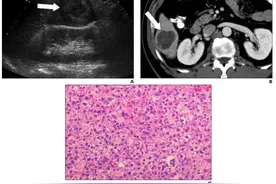

脊柱嗜酸性肉芽肿